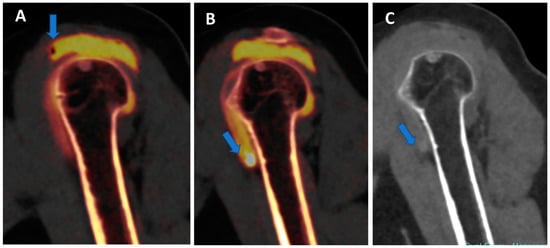

Figure 6.

Traumatic anterior shoulder dislocation with rotator cuff complete tear and Hill Sachs lesion. On the 2D 1 mm axial and coronal reconstructed VNCa images (A,B), a subtle depression of the posterior aspect of the humeral head is visible, with mild edema coded in green on the superimposed map (arrow). The 3D VNCa image (C) clearly shows the passage of contrast material in the sub-acromial space (arrow). On the coronal 1 mm reconstructed iodine map image (D), the complete rupture of the rotator cuff is beautifully confirmed (arrow). On the sagittal LNC images (E,F), it is possible to identify (arrow on (F)) and quantify (ROI on (E)) the presence of atrophy of the muscle belly.

In clinical practice, BME maps reconstructed from VNCa imaging could be employed to detect bone marrow lesions around the imaged joints. Although iodinated contrast material could generate some artifacts in the adjacent areas, the presence of BME can still be visualized. For example, in the case of shoulder trauma with doubtful dislocation, the presence of BME on the posterior aspect of the humeral head may help corroborate the diagnosis of a Hill-Sachs lesion (Figure 1 and Figure 6). In addition, BME around the joint, with or without erosions, can be found in inflammatory diseases such as septic or aseptic arthritis [31,32,33] (Figure 7).

Figure 7.

Shoulder acute crystal arthritis. On coronal STIR and T1 weighted MR images (A,B), it is possible to identify erosive changes and BME of the humeral head (arrow) with corpuscular fluid within the articular cavity. On para-coronal 2D and 3D DECT images (C,D), severe bone reabsorption with edema of the femoral head is confirmed (arrow).